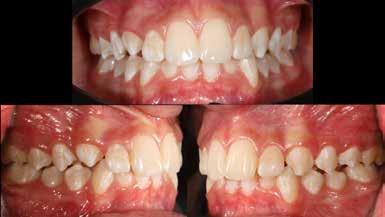

A vegyes fogazati kezelési célok a fogívek tágítása és a mandibula meziális irányú növekedésének a biztosítása volt. Fontos, hogy az ilyen típusú készülékeket nem csak éjszaka, hanem napközben is – amennyit csak lehet – hordani kell a minél hatékonyabb működés érdekében. A 18 hónapos első fázisú kezelésnek köszönhetően az alap kezelési célok megvalósultak, sikerült a class 1-es okklúziót beállítani (4-7. képek).

A második Pitts-21 fix készülékes fázis ideje 16 hónap volt (10-12. képek)

A fogszabályozás aktív fázisa után minden kezelésnél a retenció, a passzív helyben tartó fázis a kezelési eredmény megtartására rendkívül fontos!

Az Essix retainerek, az egy fogívre kiterjedő mélyhúzott sínek, valamint a felső és alsó frontfogakra orálisan ragasztott fix retainerek mellett, a harapás sagittális rögzítésében elengedhetetlen szerepe van az ún. Pitts Izom Tréning Splint-nek, amelybe a páciens élharapásban összeharap, így az megakadályozza az alsó fogsor visszamozdulását a disztálharapásos helyzetbe (13. kép)